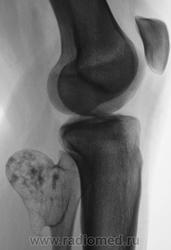

Я ранее выставлял снимки этой пациентки. Сегодня пациентка сама явилась на исследование, так как появились не резкие боли. После предыдущего исследования пациентка была консультирована в ОКБ, было рекомендовано наблюдение в динамике.

Сегодняшние снимки.

Я сравнил снимки с предыдущими, промерял изображение. На "боковой" образование, явно увеличилось в размерах.

Сегодня, меня весьма насторожило, потеря четкости контура, на участке, отмеченном стрелками, а также "выход вещества" за условный контур - красные стрелки.

Остеохондрома? Думаю, надо убирать.

Предыдущие снимки.

Конечно, укладки несколько отличаются, что естественно, но все таки локальное, как бы, "выбухание" и легкая неровность конутра на контрольном снимке весьма подозрительны....

Снимки "до" предыдущих снимков.

Все таки кажется, что конур был ранее более ровным.

Первые снимки - сегодня.

Вторые снимки - конец - 2008 года.

Третьи снимки - 2007 год.

Еще более ранние снимки.

Не знаю Борис Владимирович. Я, промеривал по боковой, сегодняшнюю и предыдущую. У меня вышел - рост.